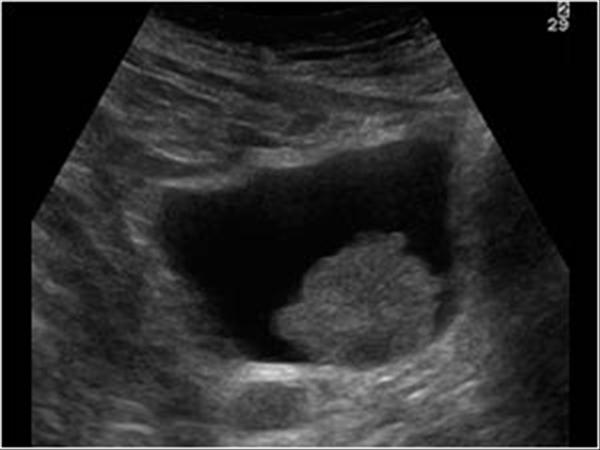

Mesane kanseri ultrasonda çıkar mı? Mesane kanserinde ultrason bulguları, tümörün boyutuna, yerleşimine ve mesane duvarıyla olan ilişkisine bağlıdır. Tipik ultrason bulguları şunları içerebilir:

- Mesane iç yüzeyinde kitle: Mesanenin iç boşluğuna doğru çıkıntı yapan, düzensiz sınırlı bir kitle görülebilir.

- Duvar kalınlaşması: Mesane duvarında lokalize veya diffüz kalınlaşma, kanserin derin dokulara yayılımını düşündürebilir.

- Ekojenik kitleler: Kitleler genellikle hiperekojenik (daha parlak) görünür ve mesane sıvısından ayırt edilebilir.

- Mesane içi pıhtılar: Tümör kaynaklı kanama sonucunda mesane içinde kan pıhtıları izlenebilir.